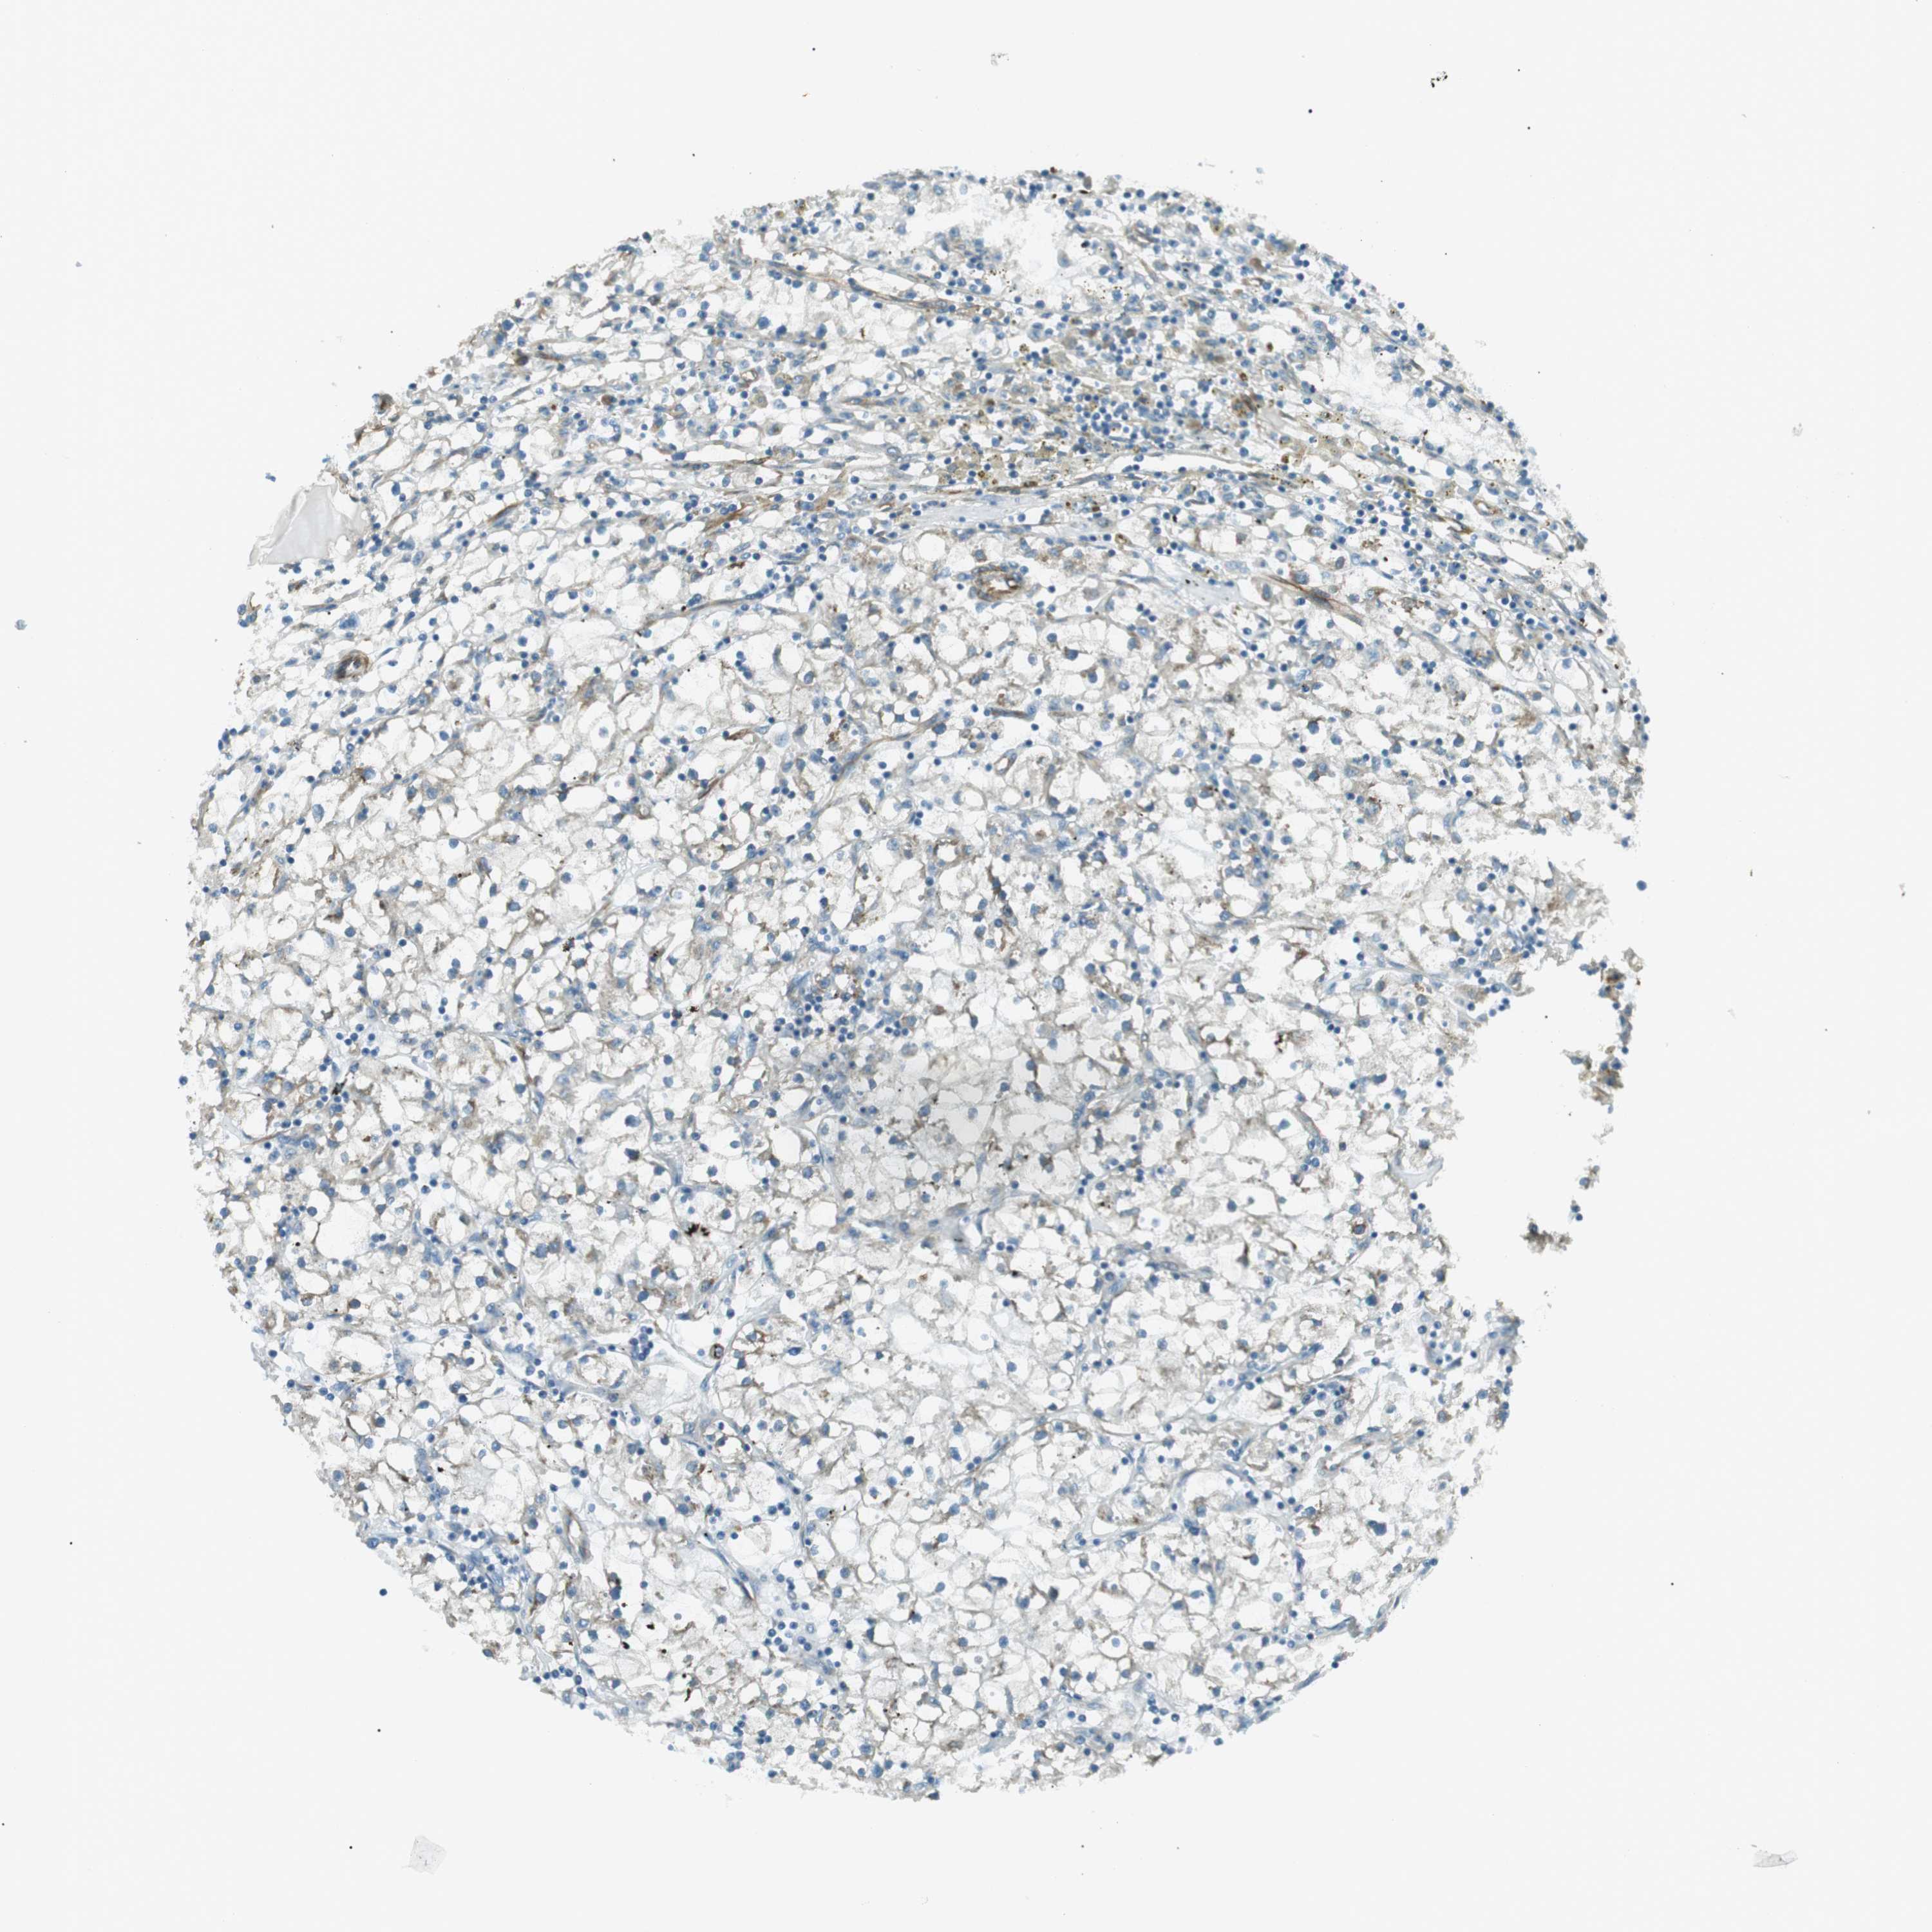

CANCER RENAL CANCER Show tissue menu

KICH TCGA KIRC TCGA KIRC VALIDATION KIRP TCGA PROTEIN RCC CPTAC PROTEIN EXPRESSION